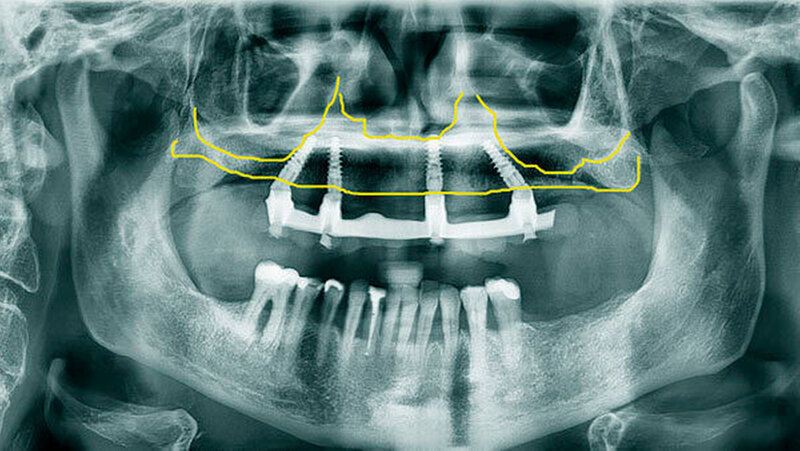

Eine erhebliche Erweiterung der Indikation des All-on-4 Konzeptes konnte durch den Einsatz von Zygoma-Implantaten erzielt werden. Zygoma-Implantate werden im Os zygomaticum verankert und erreichen auch in Situationen mit starker Kieferkammatrophie eine hohe Primärstabilität. Herkömmliche augmentative Verfahren können so vermieden werden. Zygoma-Implantate wurden zunächst bei Patienten mit besonderen Dysplasien im Kieferbereich und bei Tumorpatienten nach Resektion von Kieferanteilen eingesetzt. Balshi war einer der ersten Kliniker, der mit speziell gestalteten Implantaten entsprechende Fälle versorgte. Die Übertragung des All-on-4 Konzeptes auf Zygoma-Implantat-getragene Versorgungen ist insbesondere mit dem Namen Malavez verbunden, die sich sehr um diese Technik verdient gemacht hat. Dieses Konzept auf Zygoma-Implantaten wird angewendet in Fällen mit ausgeprägter Kieferkammatrophie im Oberkiefer (Abbildung 4a). Die Zygoma-Implantate werden in aller Regel in ITN inseriert. Lediglich ein externer Sinuslift ist als augmentative Maßnahme notwendig (Abbildungen 4b und c). Durch dieses Vorgehen können aufwändige augmentative Verfahren umgangen werden. Die prothetische Versorgung der Zygoma-Implantate entspricht dem Vorgehen wie beim All-on-4 Konzept und erfolgt einen Tag postoperativ. Erreicht wird, wie beim ursprünglichen All-on-4 Konzept, eine festsitzende Sofortversorgung (Abbildungen 3 und 4d).

Während die Behandlungszeit bei komplexen Augmentationen ein Jahr und mehr betragen kann, ist bei Verwendung von Zygoma-Implantaten eine festsitzende Sofortversorgung möglich. Eine Kombination von konventionellen Implantaten bei lokal ausreichendem Knochenangebot mit Zygoma-Implantaten bei lokal unzureichendem Knochenangebot ist möglich.